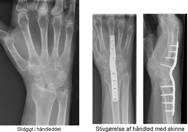

Slidgigt i håndled

Slidgigt i håndleddet opstår typisk som følge af et brud i spolebenet eller brud på en af håndrodsknoglerne. Tilstanden medfører smerter i håndleddet. For mange patienter er en stivgørende operation en god løsning.

Stivgørelse er for mange personer en god løsning. I mange tilfælde er det angrebne led allerede blevet mere eller mindre stift inden operationen, så forskellen i funktion vil ikke blive meget ændret, men det er smertelindringen, der er gevinsten.

Efter stivgørelse af håndleddet kan du ikke bevæge håndleddet op og ned samt fra side til side. Drejebevægeligheden af underarmen og bevægeligheden af fingrene bevares.